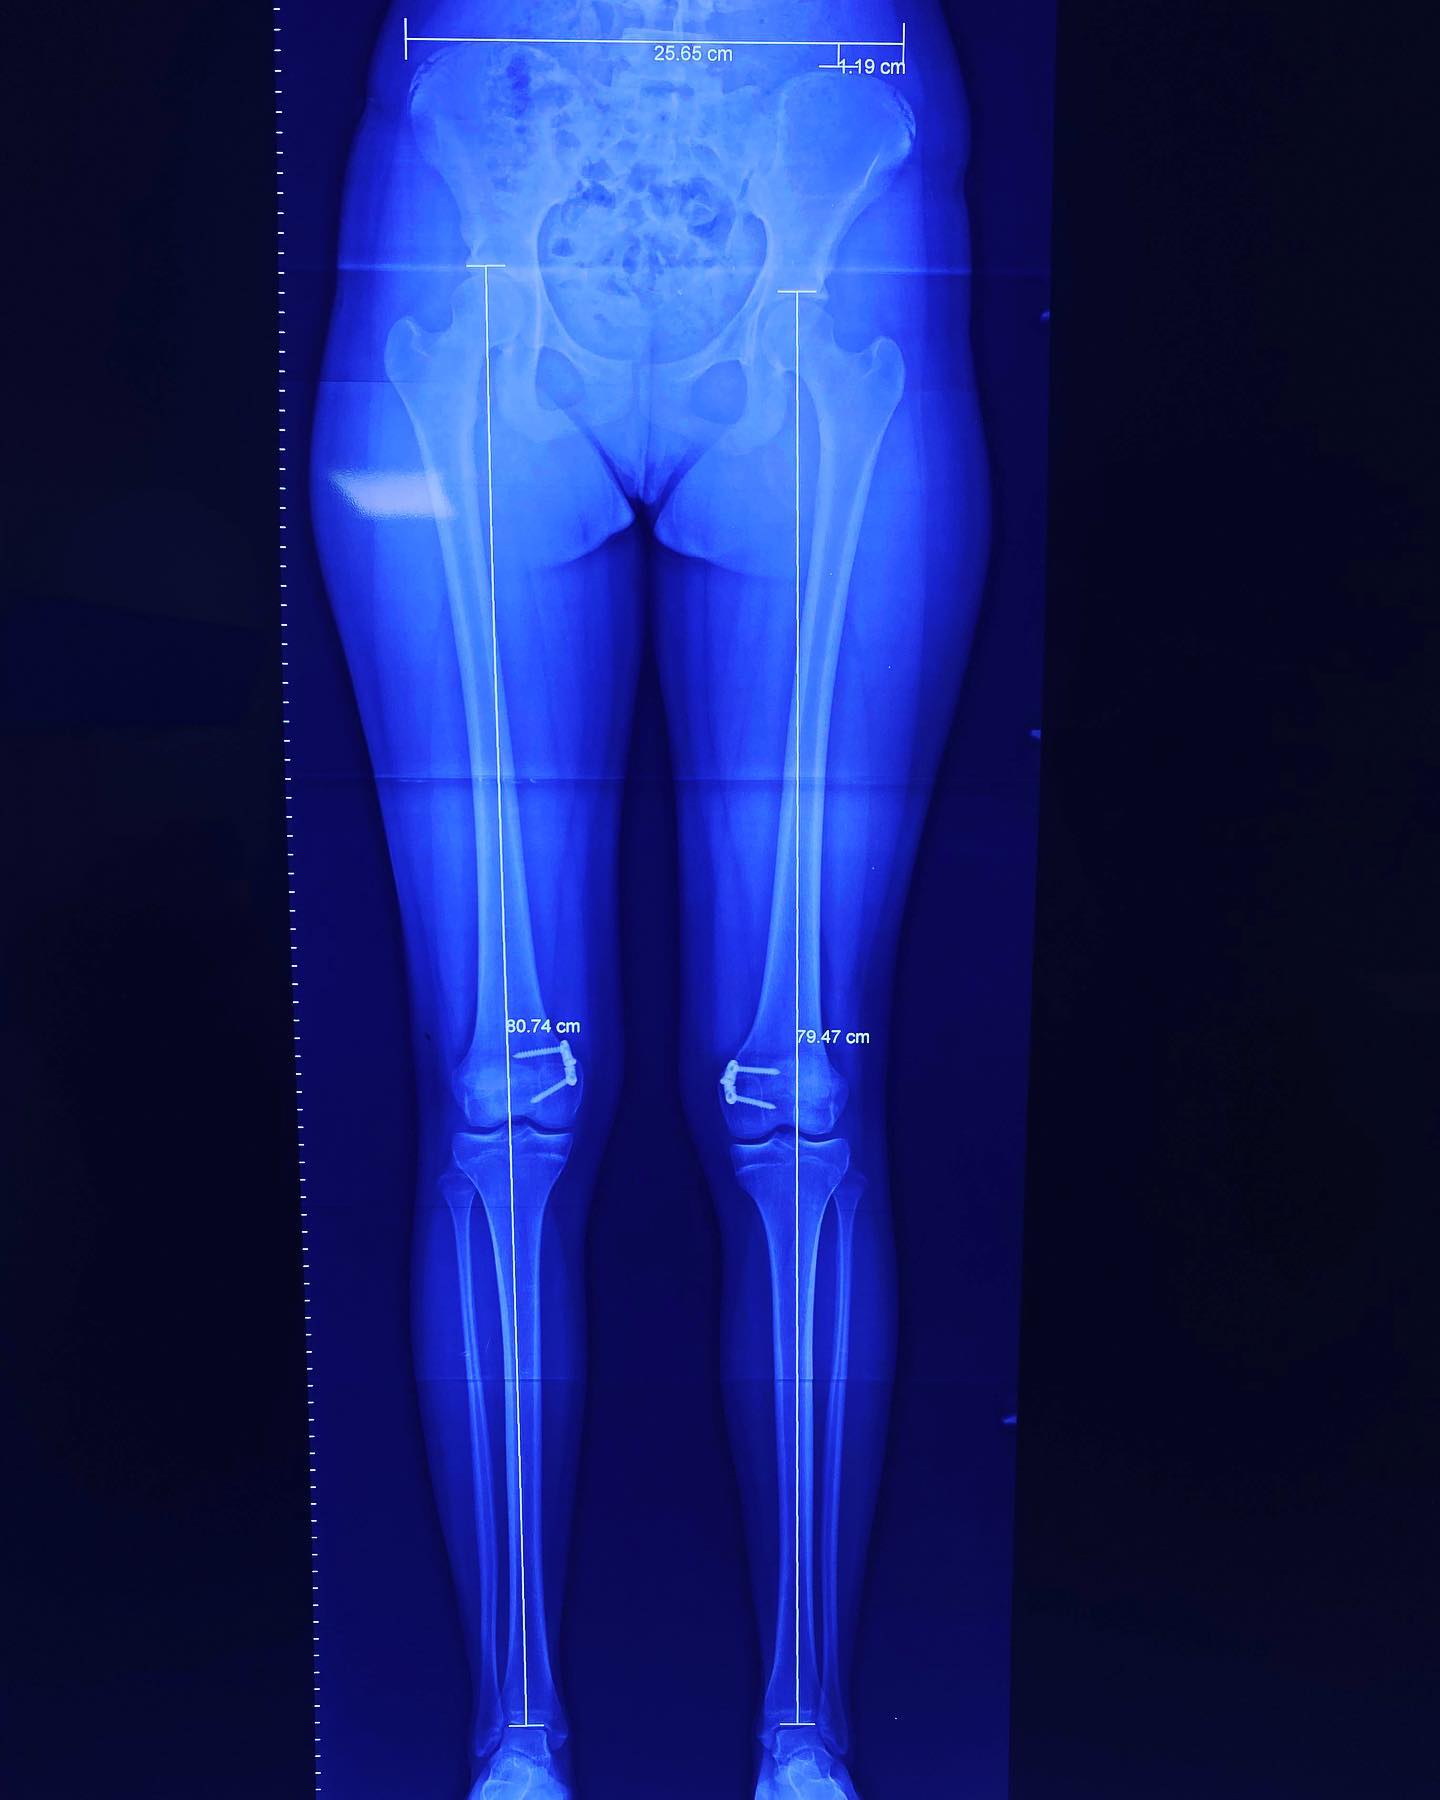

deformidad rodillas en valgo

Ella es mi pacientita Danna, de 13 años. Vino a consulta por una deformidad muy común: "Rodillas en Valgo”. Por suerte, llegó a tiempo y logramos corregirla al 💯. ¡Felicidades, Danna! Ahora sí, ¡a darle al gym! 💪